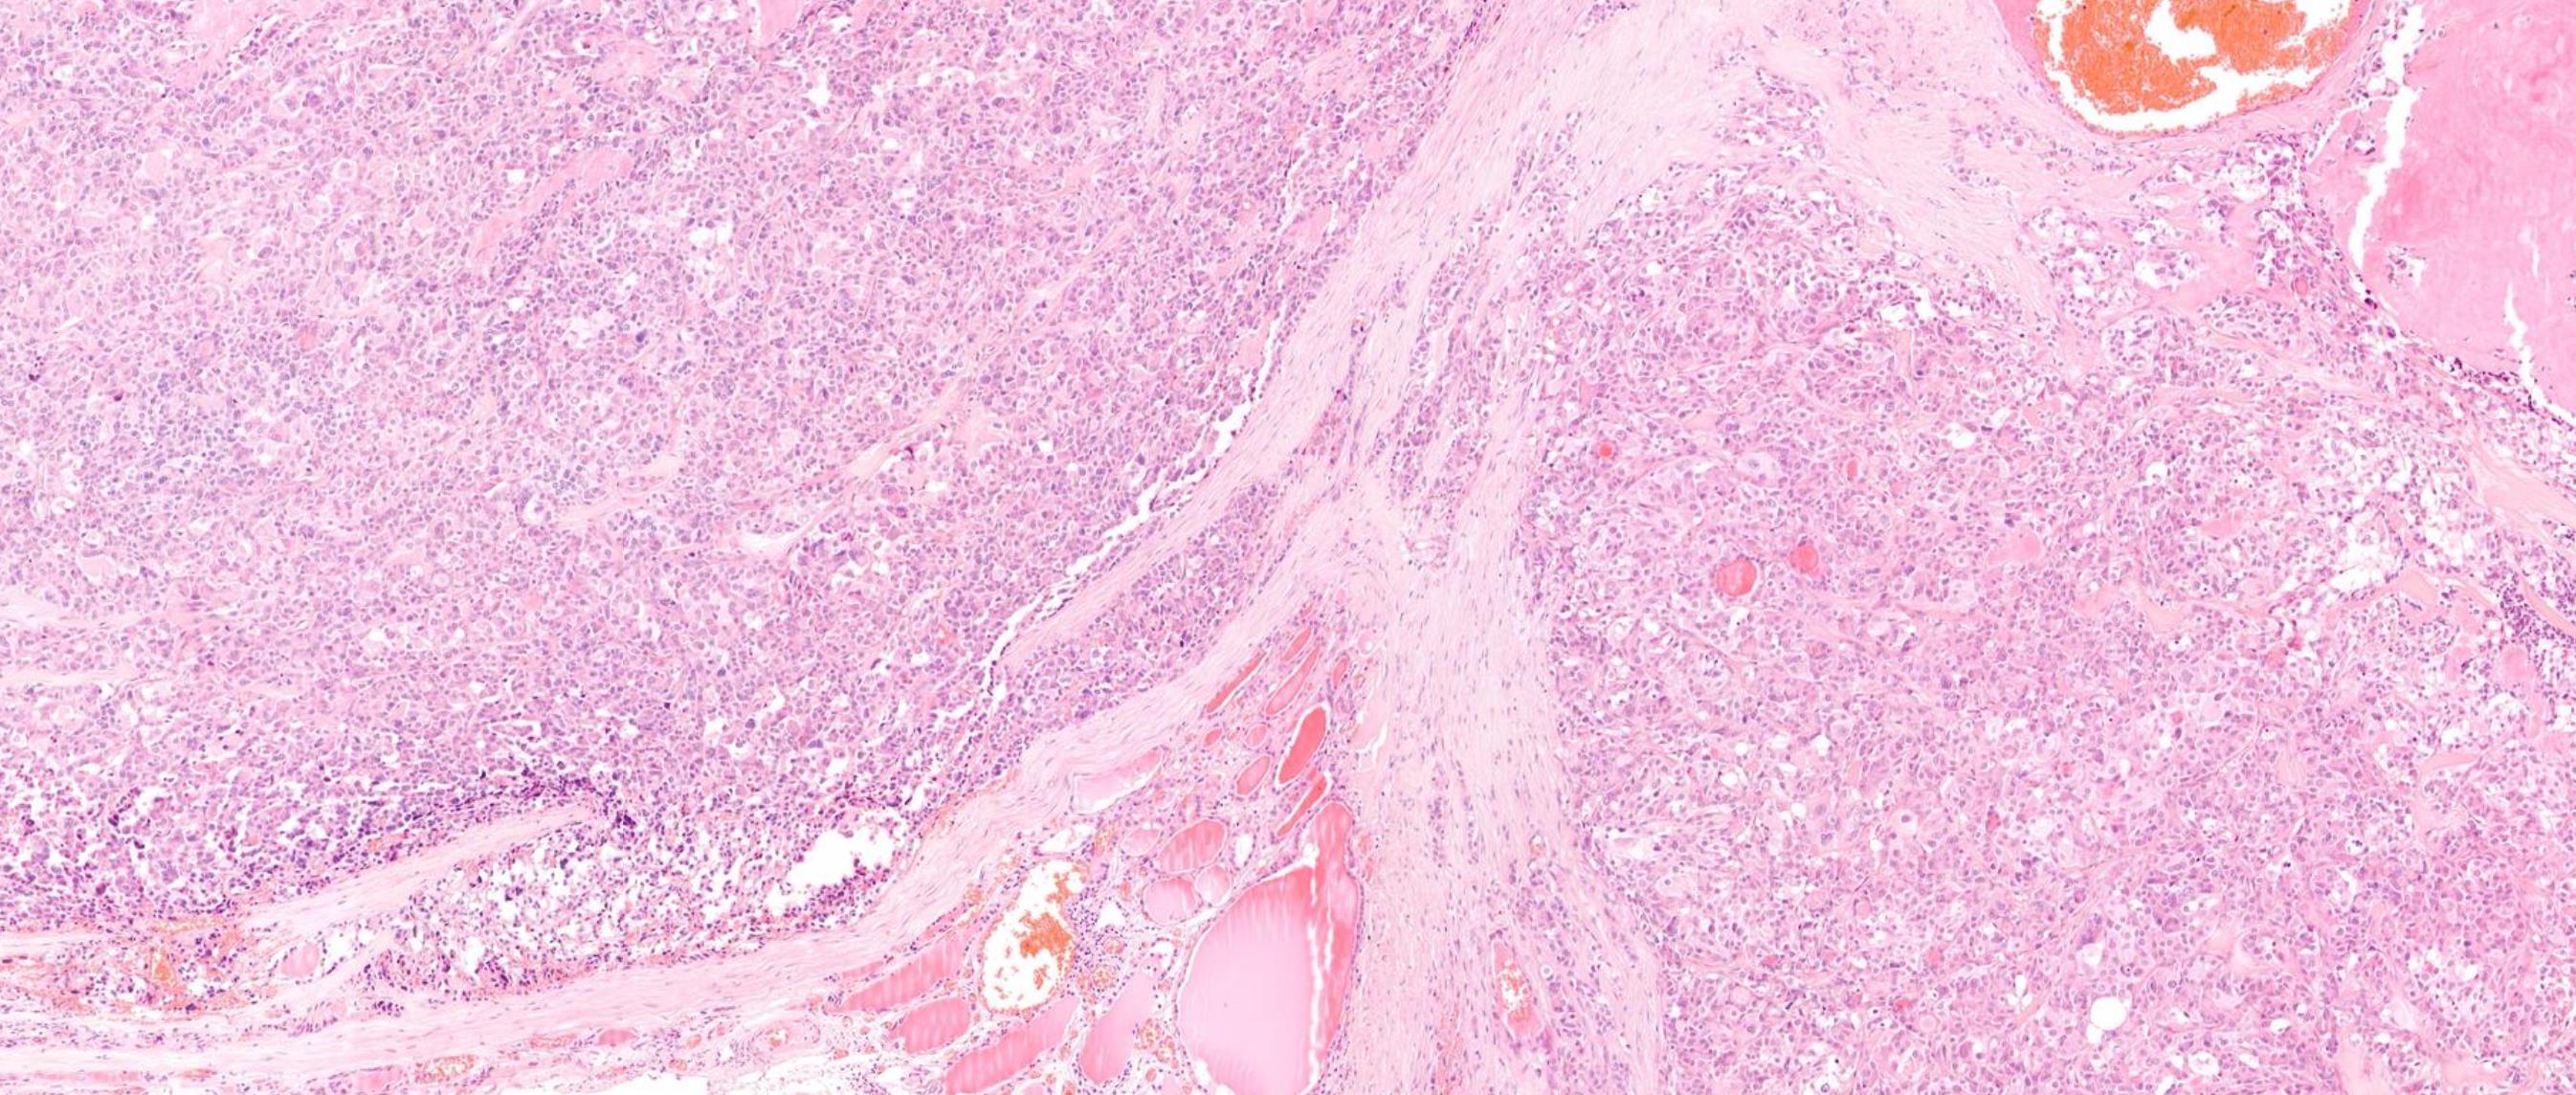

Case 1 59-year-old Female, Thyroid nodule.

Case 1 Diagnosis

Medullary carcinoma

Discussion • Sporadic- commonest, older age, no c cell hyperplasia, best prognosis • Hereditary (25%)- RET mutation, poor prognosis • MEN2A/2B associated- c cell hyperplasia, slightly older age, aggressive • Familial medullary thyroid carcinoma (FMTC) syndrome, von Hippel-Lindau disease or neurofibromatosis • Bilateral, multicentric in syndromic patients